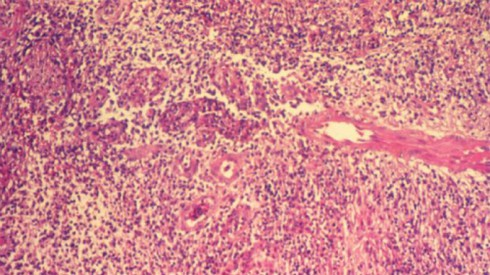

Mô nhiễm bệnh Donovanosis nhìn qua kính hiển vi. Ảnh: Live Science. |

Giai đoạn đầu, bộ phận sinh dục bị nhiễm vi khuẩn sẽ xuất hiện các vết loét nhỏ không gây đau. Dần dần, các vết loét nhỏ này lớn lên và hình thành những vết sưng đỏ dễ chảy máu. Donovanosis có thể phá hủy mô sinh dục và làm cho da xung quanh khu vực này nhạt màu đi.

"Căn bệnh gây tổn thương và phân hủy da vì thịt của bệnh nhân sẽ tự ăn mòn", dược sĩ Shamir Patel từ hệ thống nhà thuốc trực tuyến Chemist-4-U (Anh) cho biết. Ở các giai đoạn sau, triệu chứng của Donovanosis tương đối giống các bệnh ung thư bộ phận sinh dục.